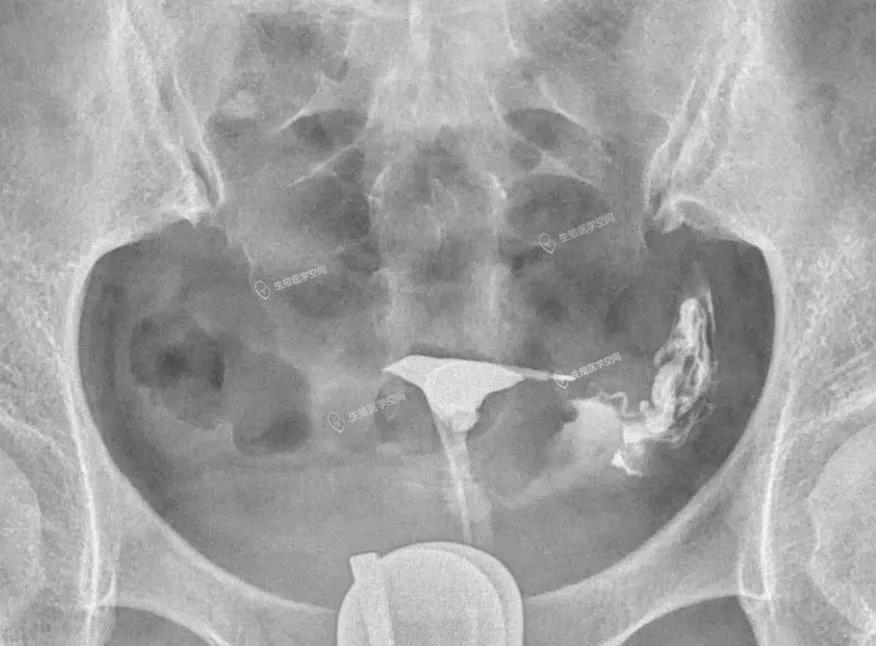

病例1 女 28岁 原发不孕,子宫输卵管造影发现双侧输卵管间质部阻塞,为结核性输卵管闭塞,不管是宫腹腔镜或放射科的介入再通术都疏通不成功。男方检查均正常。于是做试管婴儿。37周多剖宫产一对双胞胎。